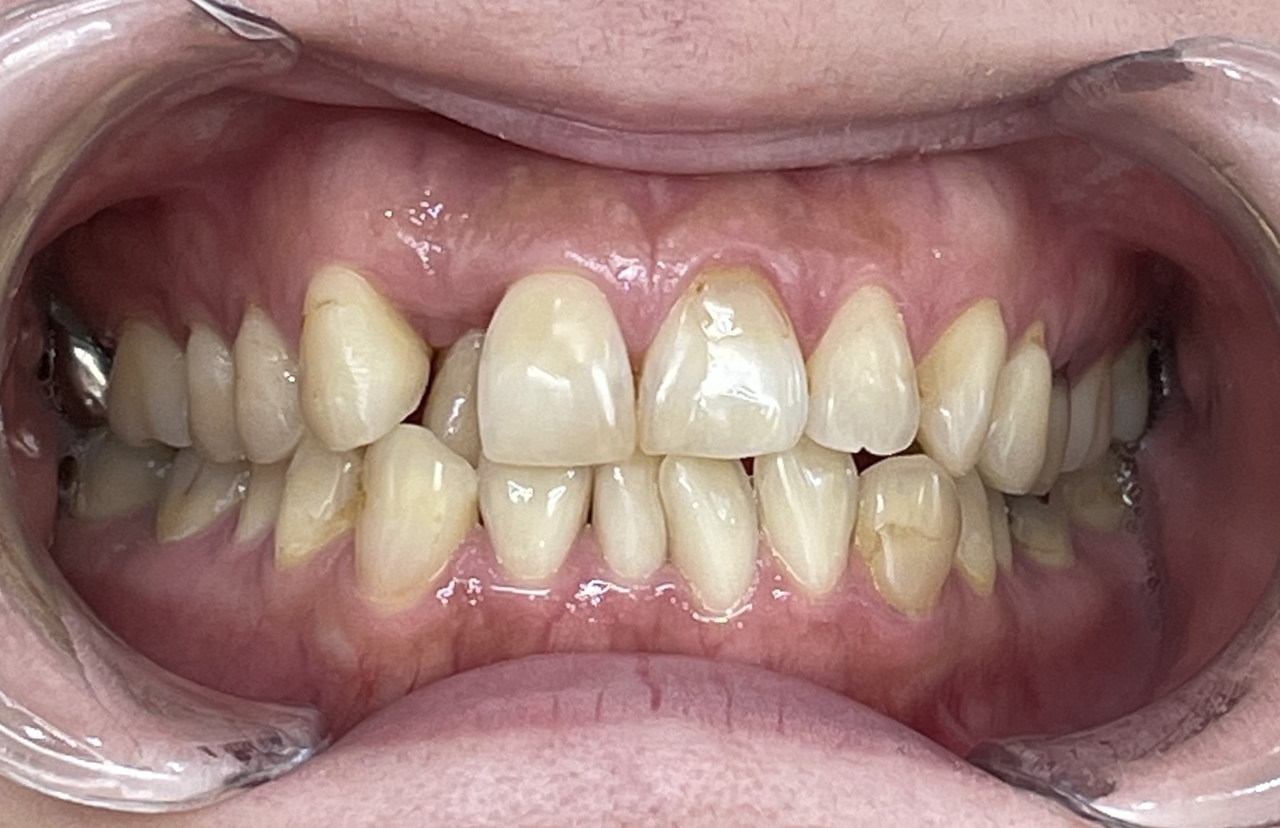

Before

After

矯正の種類 / invisalign GO

年齢・性別 / 30代女性

主訴  /  叢生、交叉咬合

治療期間 / 17ヶ月

費用 / 簡易検査 5,000円(税別) 精密検査 30,000円(税別)

両顎マウスピース 450,000円(税別) 両顎リテイナー料 60,000円(税別)

※マウスピース交換時別途調節料5,000円(税別)

副作用 / 口内炎・歯の移動に伴う痛み・知覚過敏 ※数日で収まる場合が多いです

リスク / 後戻り防止の為、夜のみマウスピースで保定を指示